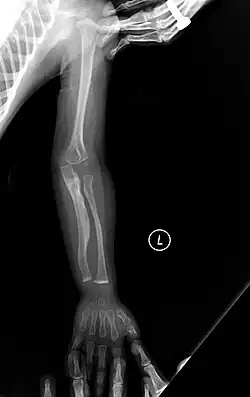

The main symptom of osteogenesis imperfecta is fragile, low mineral density bones; all types of OI have some bone involvement.[5] In moderate and especially severe OI, the long bones may be bowed, sometimes extremely so.[28] The weakness of the bones causes them to fracture easily—a study at the Endocrine Unit at the National Institute of Child Health in Karachi, Pakistan found an average of 5.8 fractures per year in untreated children.[29] Fractures typically occur much less after puberty, but begin to increase again in women after menopause and in men between the ages of 60 and 80.[1]: 486

Diagnosis is typically based on medical imaging, including plain X-rays, and symptoms. In severe OI, signs on medical imaging include abnormalities in all extremities and the spine.[97] As X-rays are often insensitive to the comparatively smaller bone density loss associated with type I OI, DEXA scans may be needed.[5]: 1514